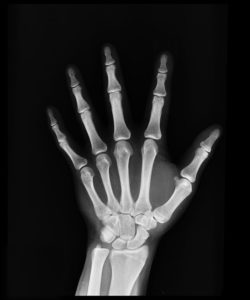

Každý úraz má jinou váhu. Na některý stačí naše domácí dezinfekce, náplast a oblíbené obinadlo, jiné si vyžadují lékařský zákrok. Asi nejčastějšími úrazy, které už alespoň jednou zažila spousta z nás, jsou zlomeniny nebo naštípnuté kosti. Zlomeninu pozná každý člověk poměrně snadno. Jednak je doprovázena velkými bolestmi v postižené části a jednak se kolem místa zlomeniny vytvoří otok a naše kůže je často namodralá. Mimo to často cítíme, nebo dokonce slyšíme pohyb úlomků kostí, které se o sebe třou. U naštípnuté kosti už to však tak jednoduché není. Drobná naštípnutí kosti nebo velmi jemná line lomu může být někdy vidět až po dvou týdnech po jejím odvápnění. Může se tedy dost možná stát, že když navštívíme lékaře bezprostředně po úrazu, rentgen náš problém neodhalí.

Specifickou kategorii zlomenin potom tvoří dětské zlomeniny. Ti z nás, kteří měli v dětství něco zlomeného si možná více než na tu bolest vzpomenou na 4- 6 týdnů se sádrou, které po ní následovaly. Z původně bílé sádry, ze kterou jsme odcházeli z chirurgické ambulance se pak většinou stal prostor pro realizace malířských umění našich kamarádů. Zvláštním druhem dětské zlomeniny je oprosti běžné zlomenině u dospělých například takzvaná zlomenina „vrbového proutku“, která v praxi vypadá tak, že se přetrhne okostnice, ale kost se zlomí jen z jedné strany, druhá je intaktní.